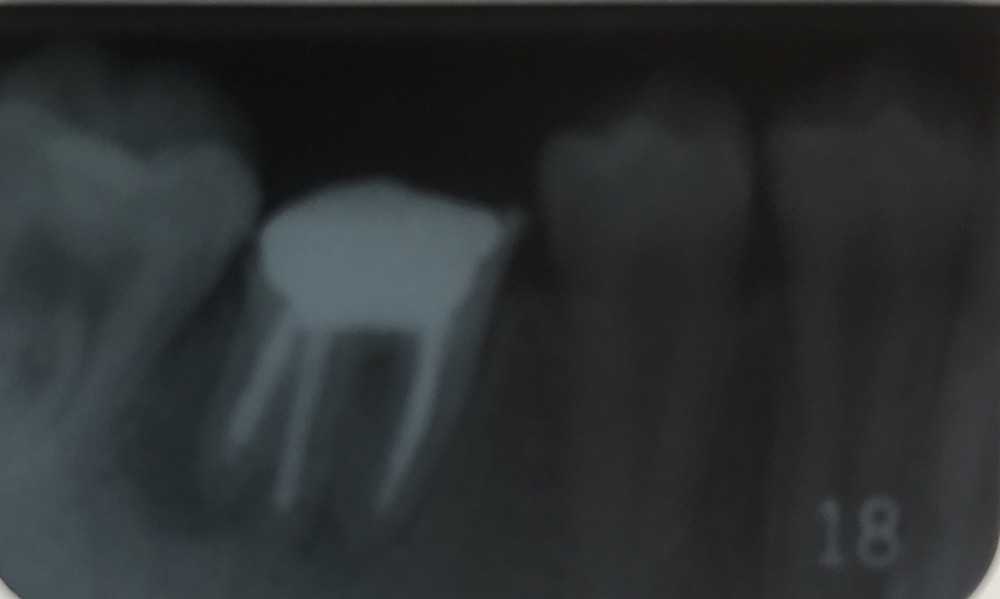

下の写真は根管充填後確認のデンタルです。

左右下6をそれぞれメタルコア築造、パラFCKセットしています。

下の写真は初診時から2年8ヶ月後のものです。

20才7ヶ月。

上の画像でも、左下6の咬合がかなり強く当たるように疑われます。

実際に咬合調整を行ないました。